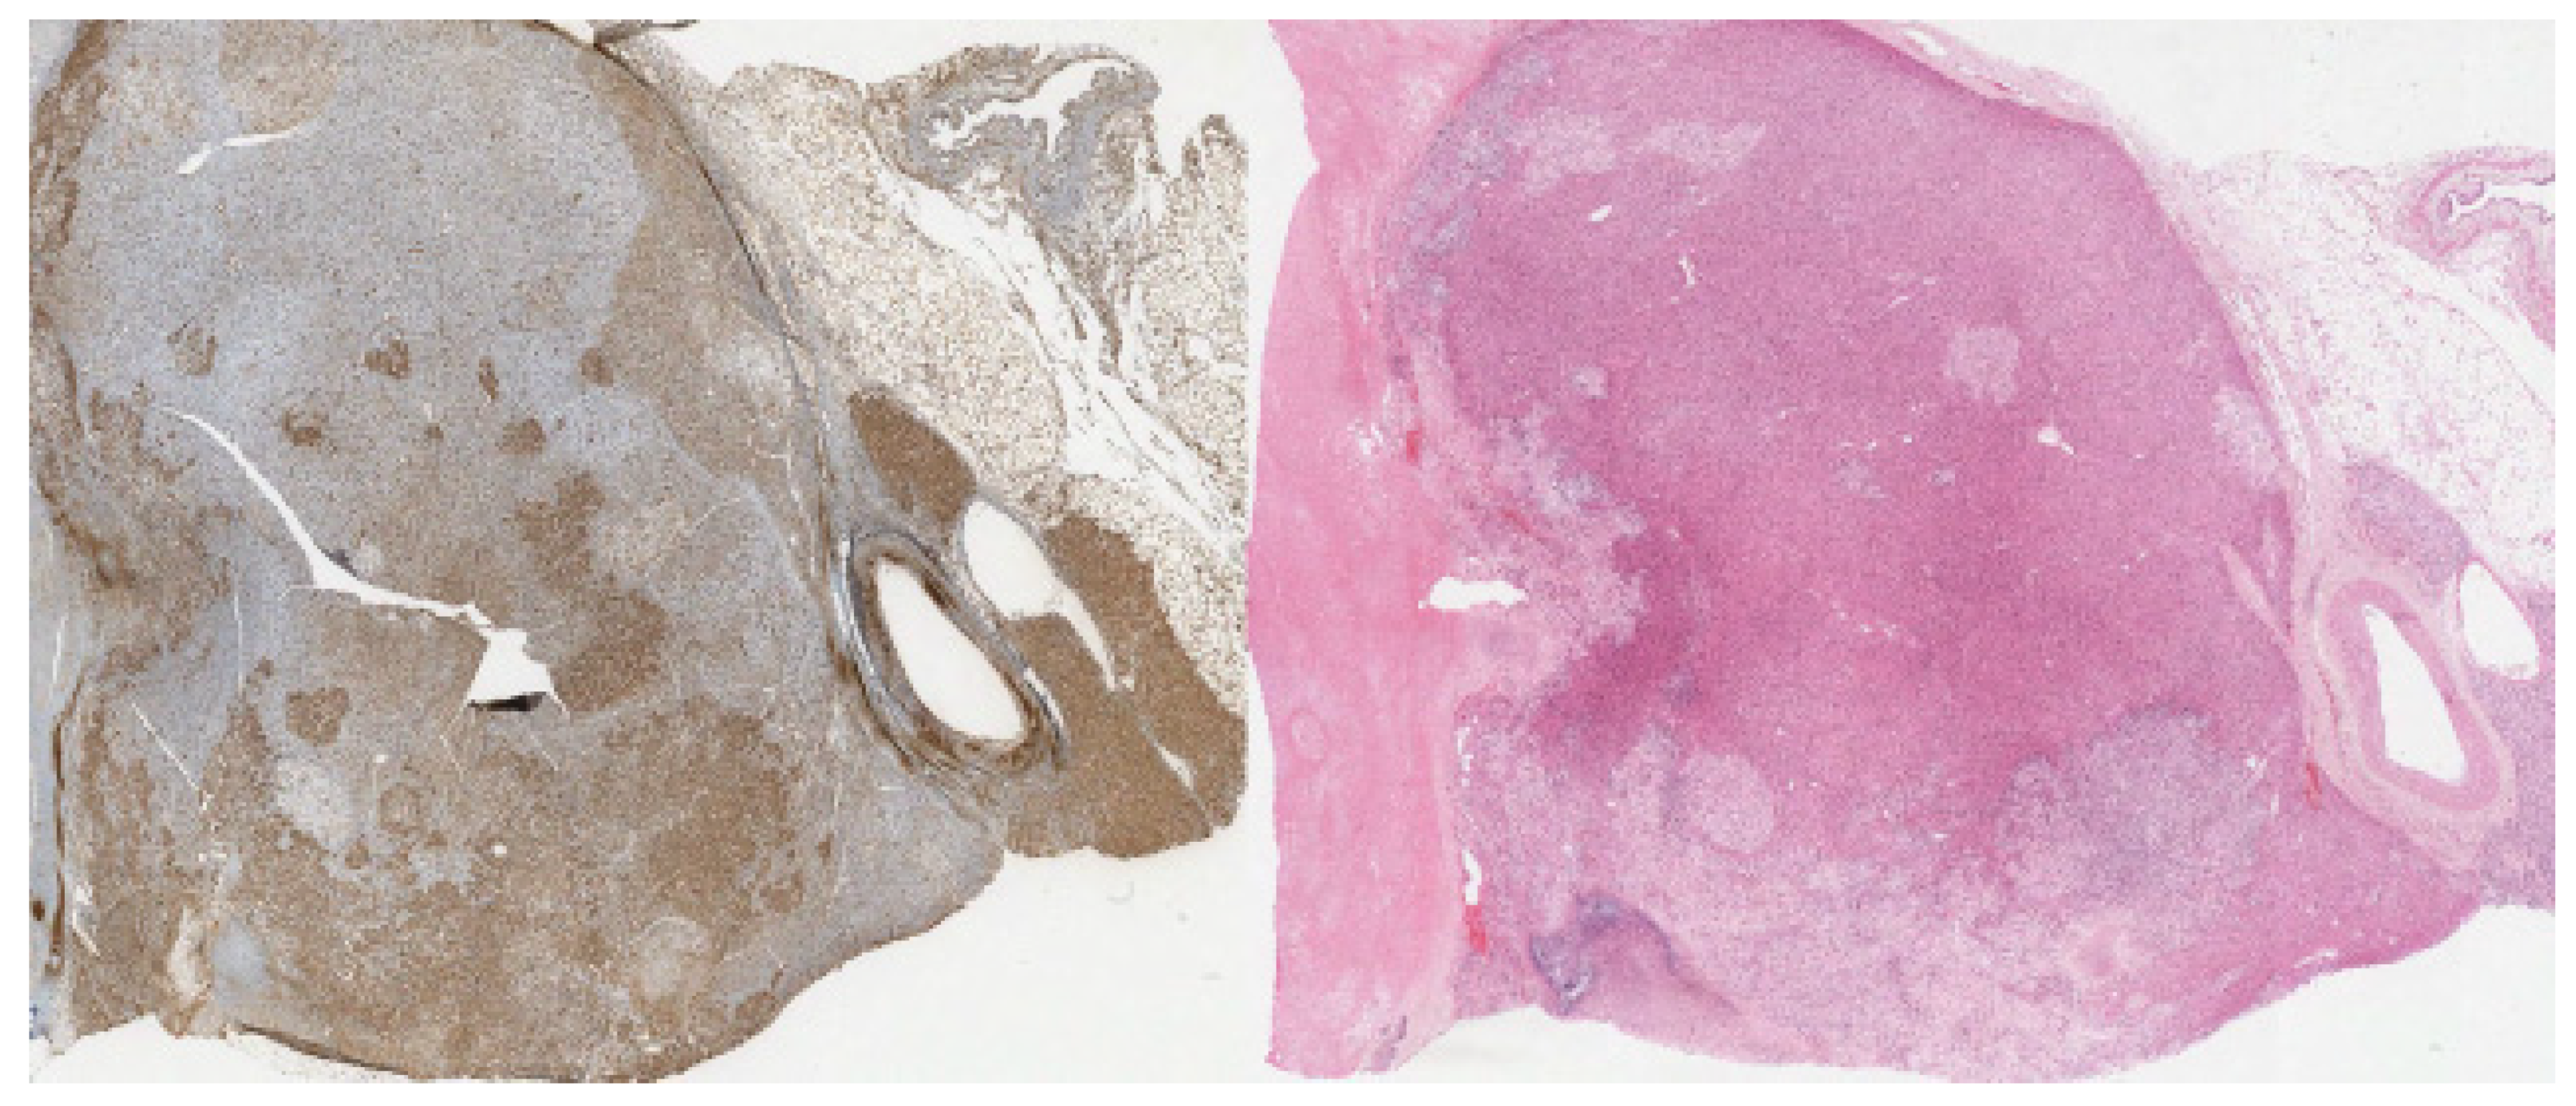

| Stain | Carcinomatous Component | Sarcomatous Component | Company | Clone |

|---|---|---|---|---|

| Calretinin | Positive | Negative | Ventana | SP65 |

| HMB-45 | Negative | Negative | Ventana | HMB-65 |

| Inhibin Alpha | Positive | Negative | Ventana | R1 |

| Synaptophysin | Positive | Negative | Ventana | SP11 |

| Myogenin | Negative | Negative | Ventana | F5D |

| Vimentin | Negative | Positive | Ventana | Vim 3B4 |

| Desmin | Negative | Positive | Ventana | DE-R-11 |

| Pax8 | Negative | Negative | Ventana | MRQ-50 |

| Pan-keratin | Negative | Negative | Ventana | AE1/AE3/PCK 26 |